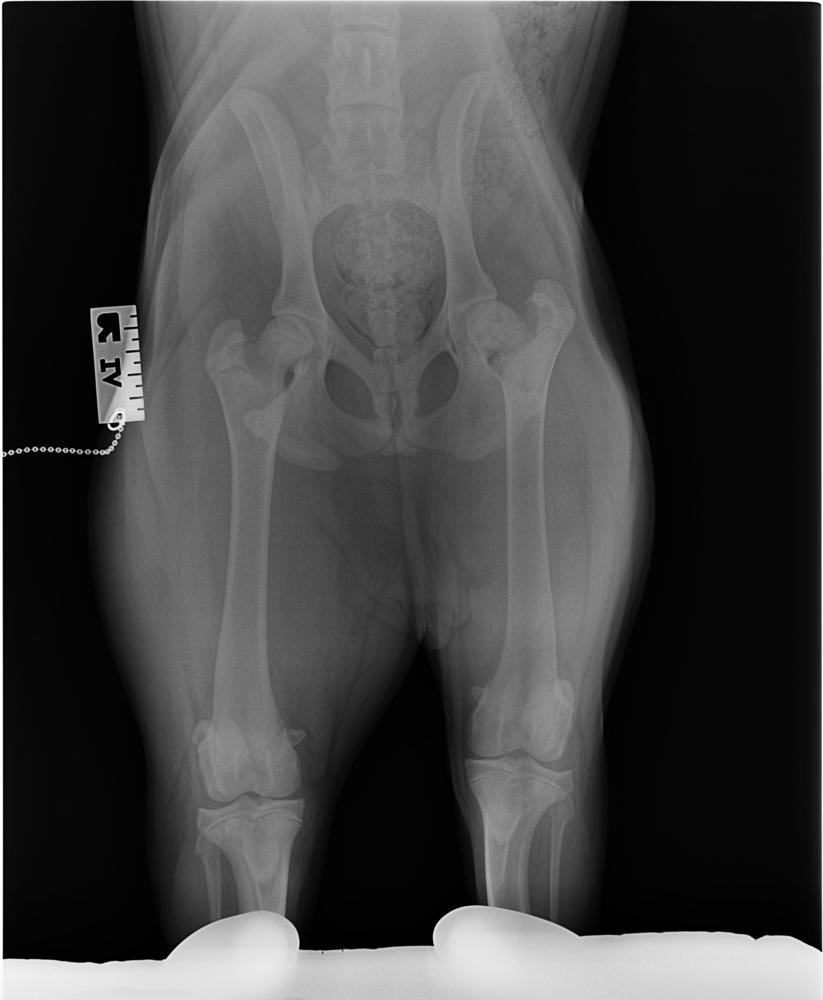

Puppy Sky suffered a painful fractured leg for months without veterinary treatment.

This veterinary examination and radiographs revealed that Sky had a fracture at the top of her left thigh bone and was suffering aseptic necrosis (death of tissue) due to trauma. The veterinarian concluded Sky would have been acutely lame and in pain when the injury was sustained and that the pain would have ongoing for a considerable amount of time.

He conceded that this would have been the incident that caused the injury and Sky had been limping all the time since. For three months Sky had been trying to keep her weight off her foot, trying to walk on her right side, and yelping when trying to jump up onto the couch and beds.